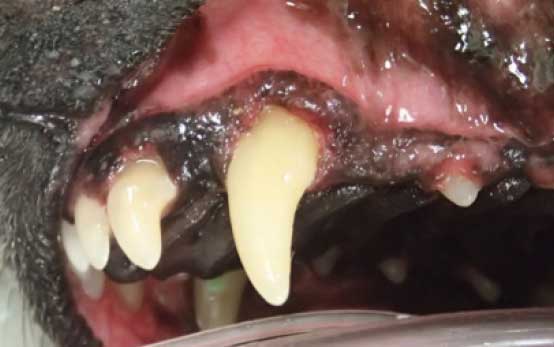

歯周病(歯肉炎)

歯周病は歯の表面に歯垢・歯石が付着した結果、歯垢中の細菌が原因で歯周組織が炎症を起こして破壊されてしまう病気です。歯肉炎は歯周病の初期に発症する状態で、歯肉に炎症が起こり、発赤や腫脹が見られます。症状が進行すると歯肉から出血を起こしやすくなります。歯肉炎の段階で治療を開始、原因を除去すれば元の状態に回復できます。

歯科処置前の所見

- 重度の歯垢・歯石の付着

- 動揺なし

- 歯肉の腫脹あり

- 歯周ポケット浅い、歯肉の退縮あり